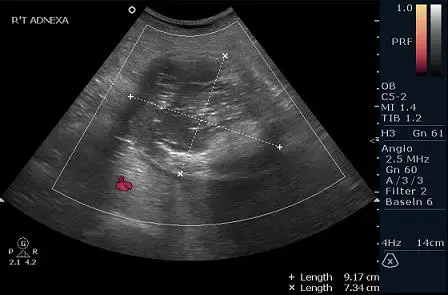

30歲女性,在健康檢查時,意外在骨盆超音波下,發現如圖所示之腫塊,最有可能的診斷為何? 圖片描述

該張經腹部超音波圖顯示右側附件區約 9.2×7.3 cm 的複雜性囊性和實質混合腫塊。可見大量高迴聲區,伴有強烈後方聲波衰減,後方腫塊邊界無法辨識,呈現典型的 “tip‐of‐iceberg” 現象;腫塊內亦見不規則高迴聲結節,暗示含有脂肪、毛髮或鈣化等成分。缺乏單純的低回聲“ground‐glass”表現,也未見細密的“lace‐like”纖維網狀迴聲。

• 選項C 畸胎瘤:成熟囊性畸胎瘤常見複雜性迴聲,包含高度反射的脂肪、毛髮及鈣化物;Rokitansky 嵌節(echogenic mural nodule)及 tip‐of‐iceberg 簇狀聲影為關鍵徵象,亦可能見 dot‐dash pattern。上述超音波圖正顯示高迴聲結節與明顯後方聲衰減,吻合 dermoid 特徵 (radiologykey.com, ncbi.nlm.nih.gov)。

超音波中若看到卵巢腫塊內部分明高迴聲結節並伴隨後方聲波強烈衰減(tip‐of‐iceberg)、echogenic mural nodule,最符合成熟囊性畸胎瘤(dermoid cyst)的影像特徵,其內容含脂肪、毛髮與鈣化成分,易產生此類混合迴聲與聲影。其他選項在回聲型態上與此大相逕庭,故正確答案為 C。